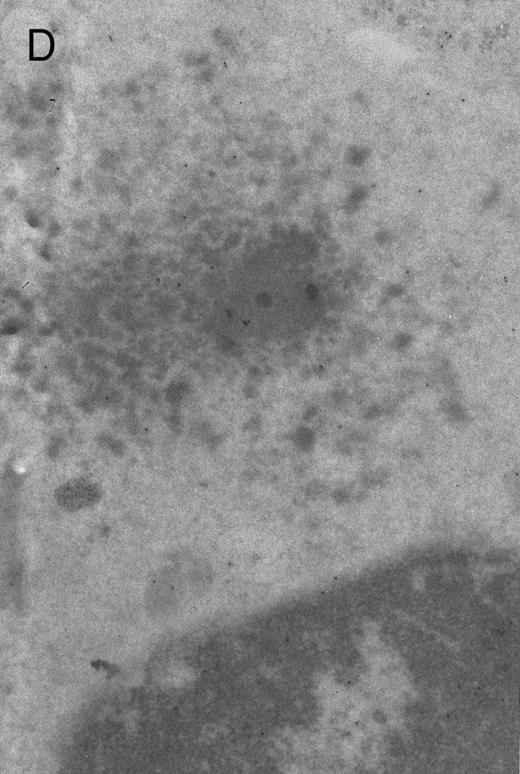

In both cases no. 1 and no. 2, electron microscope studies demonstrated electron-dense inclusions in 30% of early and late polychromatic erythroblast sections and many marrow reticulocytes. In ultrathin sections that reacted with monoclonal antibodies to either α- or β-globin chains followed by gold-labeled anti-mouse IgG, the density of gold particles over the majority of the inclusions was clearly greater than that over surrounding inclusion-free cytoplasm (Fig 3). By contrast, in sections from the two patients with β-thalassemia major, gold particles were concentrated over the inclusions following incubation with the antibody to α-globin chains, but not to β-globin chains (Fig 4A-C). The density of gold particles over inclusions in all control preparations was not greater than that over surrounding cytoplasm (Fig 4D).

Electron micrographs of erythroblastic inclusions from sections of marrow immunogold-labeled with mouse monoclonal antibody. Inclusions from a case of β-thalassemia major show a positive reaction with antibody against human α-globin chains (A, B) and no reaction with antibody against human β-globin chains (C). B shows part of the inclusion in A at higher magnification. There is virtually no labeling of inclusions in a control section that was reacted with normal mouse serum instead of a monoclonal antibody (D). Magnifications: A, × 20,000; B, × 59,000; C, × 23,000; D, × 35,000.

Prominent intra-erythroblastic inclusions were also present in both of these individuals (patients no. 1 and 2) with dominantly inherited β thalassemia. The percentage of polychromatic erythroblast sections containing inclusions in the two cases was 30%, which is considerably above the range (0.2% to 2.8%) previously reported in β-thalassemia trait.13 We have investigated the composition of the inclusions in cases no. 1 and 2 by immunoelectron microscopy using mouse monoclonal antibodies against human α- and β-globin chains and the immunogold technique. The intra-erythroblastic inclusions in the two cases reacted with both monoclonal antibodies to α- and β-globin chains, clearly indicating that these inclusions contained both types of chains. In contrast, the intra-erythroblastic inclusions found in homozygous β thalassemia reacted with the monoclonal antibody against α globin but not β-globin chains, confirming that they consisted only of precipitated α-globin chains. These data support the hypothesis that the cellular pathology underlying the dominantly inherited β thalassemias is related to the synthesis of highly unstable β-globin chains, which are not able to form functional tetramers. These abnormal β-chain variants precipitate intracellularly together with the concomitant excess α-globin chains to form large inclusions, which leads to more severe ineffective erythropoiesis than in heterozygous β thalassemia, in which much smaller amounts of precipitated globin chains are found.17